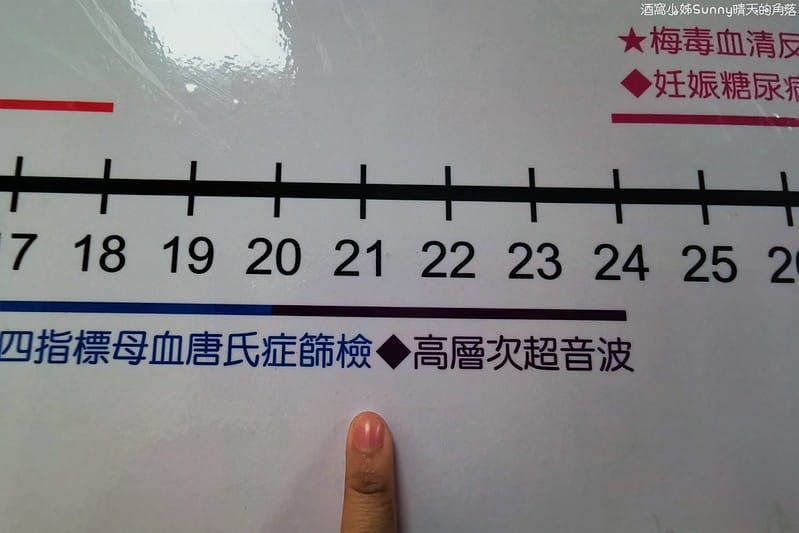

▼懷孕的孕媽咪到底要做哪些事?下圖表格簡單明瞭告訴你!

做高層次超音波的理想時間是懷孕20-24週

因為此時的胎兒頭骨、肋骨等都尚未鈣化完全

▼超音波比較容易穿透並進一步評估腦部、心臟等細部構造。